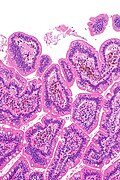

Small bowel pseudomelanosis. H&E stain.

• Dark pigment in the lamina propria macrophages.

Case 2